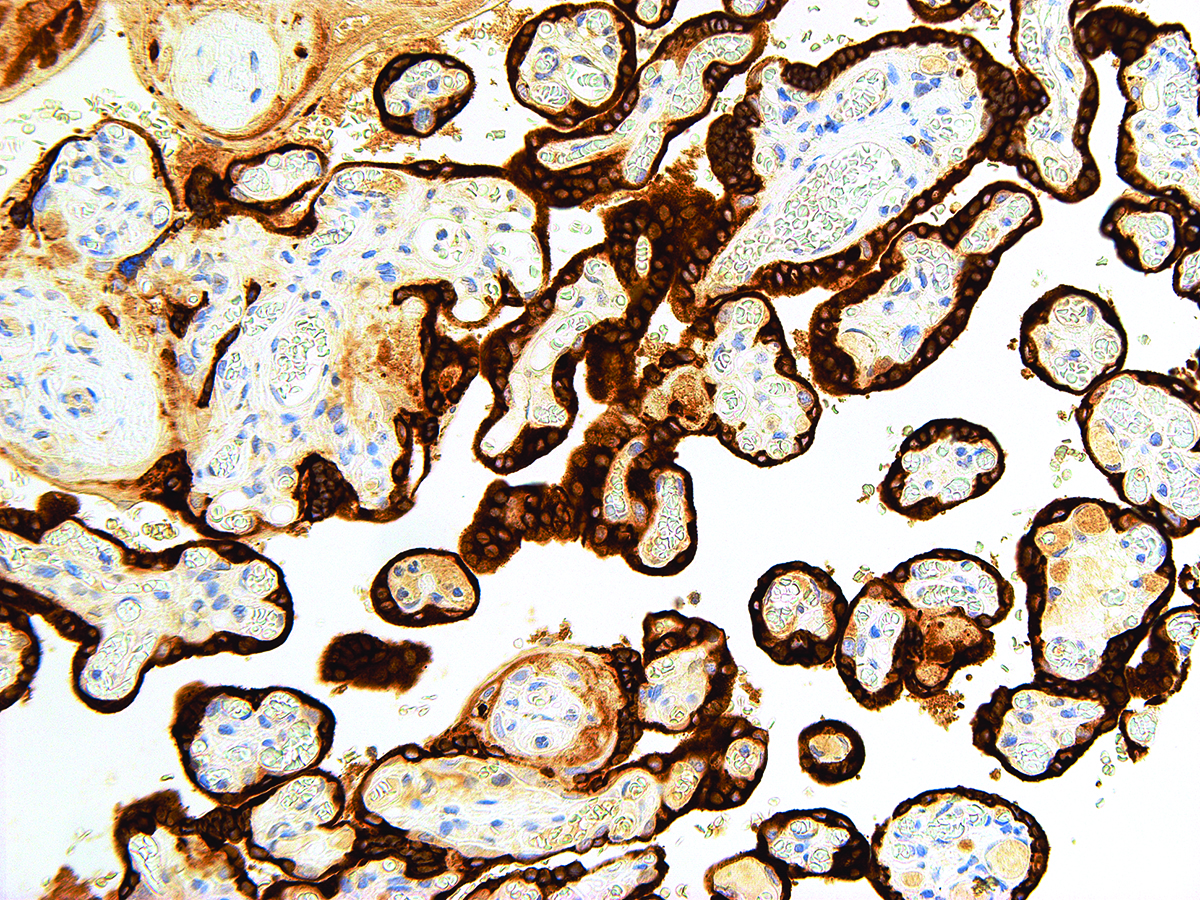

| Positive Control | Placenta |

Human Chorionic Gonadotropin (hCG) is a glycoprotein hormone produced by the trophoblastic cells of the placenta after conception. Anti-hCG is useful for identifying trophoblastic tumors, such as choriocarcinoma. hCG is also a marker for non-trophoblastic tumors such as large cell carcinoma and lung adenocarcinoma.